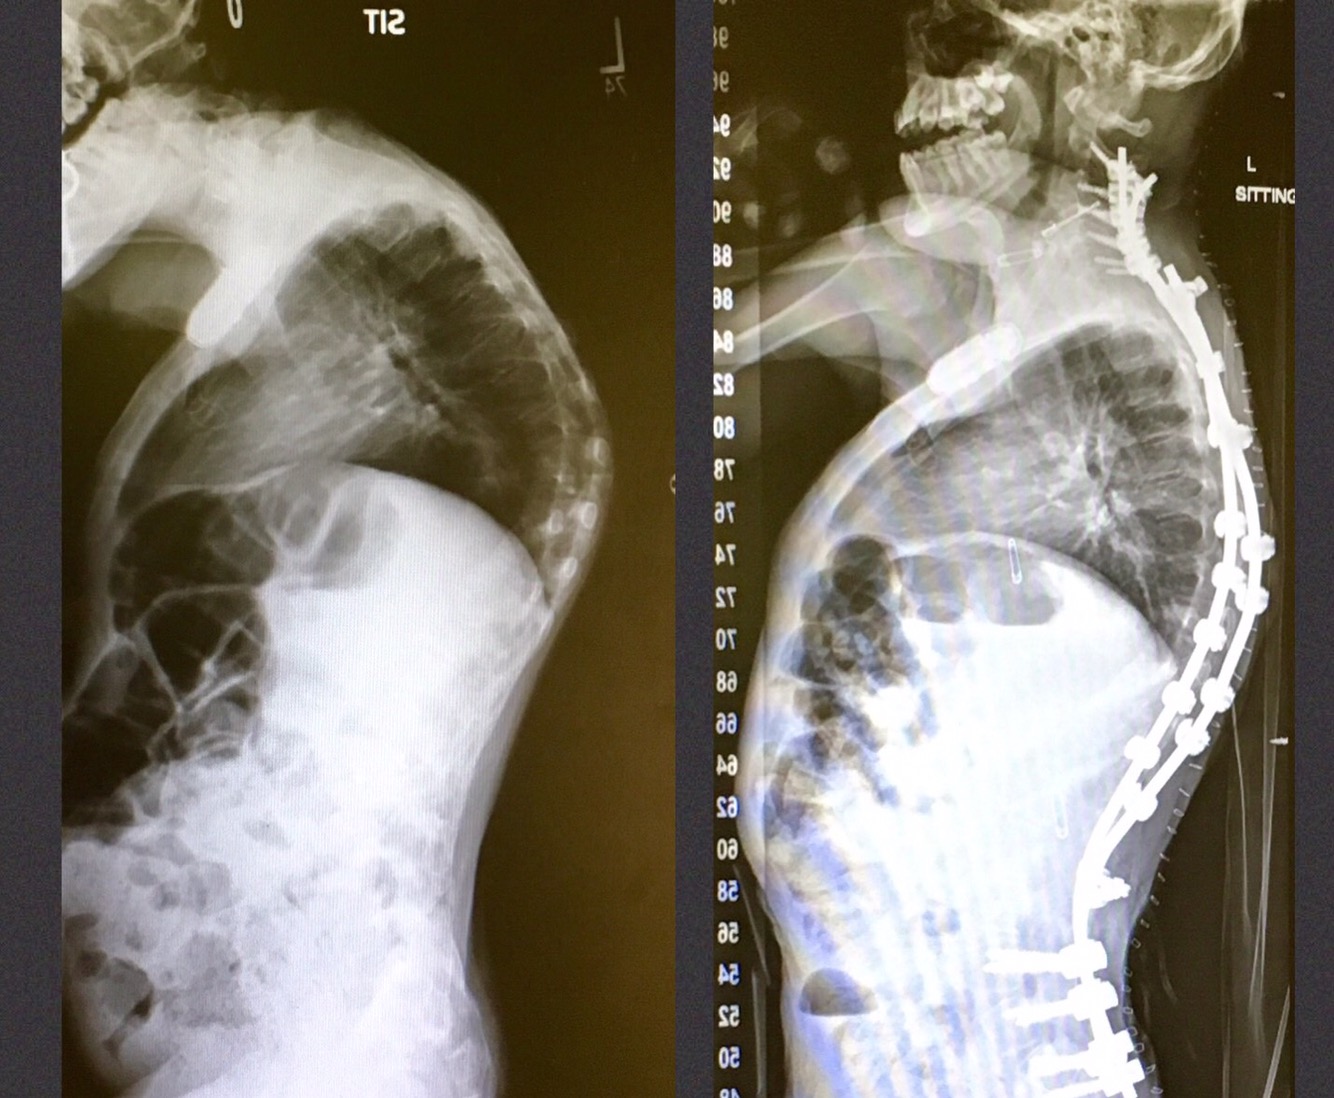

She doesn’t care for the rods being all the way up into her neck, but you can’t argue with the results. Before and After Share this: Share on Pinterest (Opens in new window) Pinterest Share on X (Opens in new window) X Share on Facebook (Opens in new window) Facebook Like Loading... Related